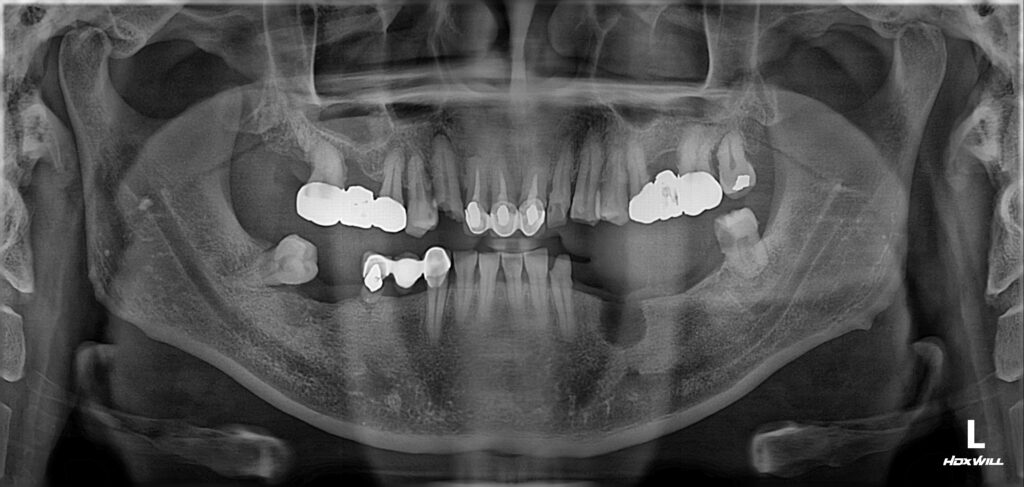

한 40대 남성이 치과에 찾아왔습니다. 치아 전체가 안 좋은데 참고 지내다가 도저히 안되겠기에 큰 맘먹고 치료받으러 오셨다고 하네요.

상태는 위와 같았습니다. 아래 앞니를 제외하고는 전부다 문제가 있는 상황이었습니다.

1. 치아 상실

2. 깊은 충치

3. 심한 잇몸 염증

4. 치아 부러짐 등

발생할 수 있는 모든 문제점들이 다 발생해 있었습니다.